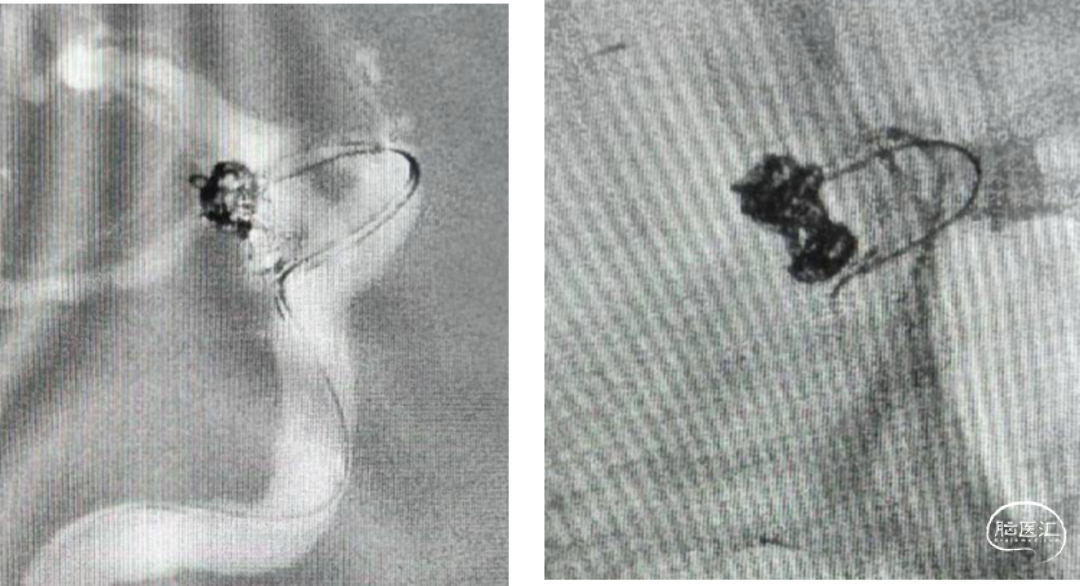

DSA:后交通动脉瘤

手术预案:后交通动脉瘤T支架辅助栓塞

微导管塑形

echelon10(45)J-7(90右偏90)-15(90);echelon10(90)J-5(45右偏90)-15(90)

工作位